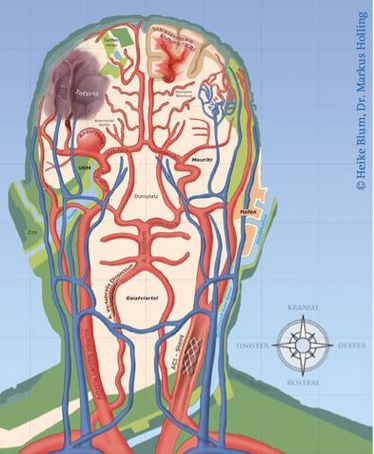

Neurovascular Day 2013

Neurovascular Day 2013